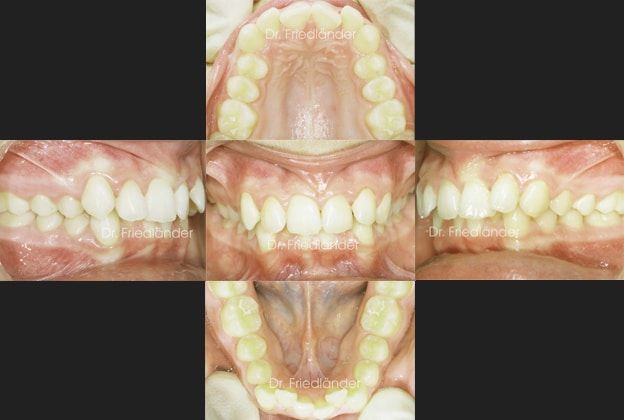

Paciente de 13 años con apiñamiento importante y unas encías muy delicadas, clase II en el lado derecho de la paciente, sobremordida aumentada. Fue tratada durante 14 meses con brackets convencionales.

Después de estudiar bien el caso he decidido junto con la paciente que la mejor opción es extraer un incisivo inferior y así generar espacio suficiente para alinear a todos los dientes y no perjudicar la encía o incluso mejorar el estado de las encías en la parte anterior de abajo. Si en este caso no se hubiera hecho una extracción los más probable es que habría terminado con recesiones gingivales en los caninos (colmillos).

Detalle de las encías tan delicadas:

se puede observar que las raíces de los colmillos y de algún incisivo casi se transparentan por la encía. (los círculos negro marcan la encía delicada)

Se colocaron brackets convencionales y se hizo la extracción de un incisivo inferior.